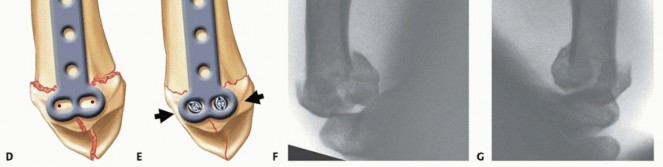

Fixation Strategies for Rolando and Comminuted Patterns

Rolando fractures present a significantly higher degree of complexity. The classical Y or T pattern often precludes simple lag screw fixation. In these instances, mini-fragment plating is the gold standard. T-plates or specialized condylar plates are contoured to fit the complex geometry of the metacarpal base. The articular fragments are first reduced and provisionally pinned, essentially converting the complex intra-articular fracture into a simpler two-part extra-articular fracture. The plate is then applied to buttress the articular fragments and bridge the metaphyseal comminution to the diaphysis.

In cases of severe, non-reconstructable articular comminution where internal fixation is impossible, joint-spanning external fixation combined with limited internal fixation (K-wires) is utilized. The external fixator relies on the principle of ligamentotaxis to restore length and align the articular fragments. Pins are placed in the trapezium (or radius) and the thumb metacarpal shaft, distracting the joint to allow for secondary bone healing while preventing collapse.